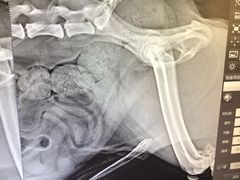

• 永康动物医院

• -永康动物医院

晓样样 | 20-07-03